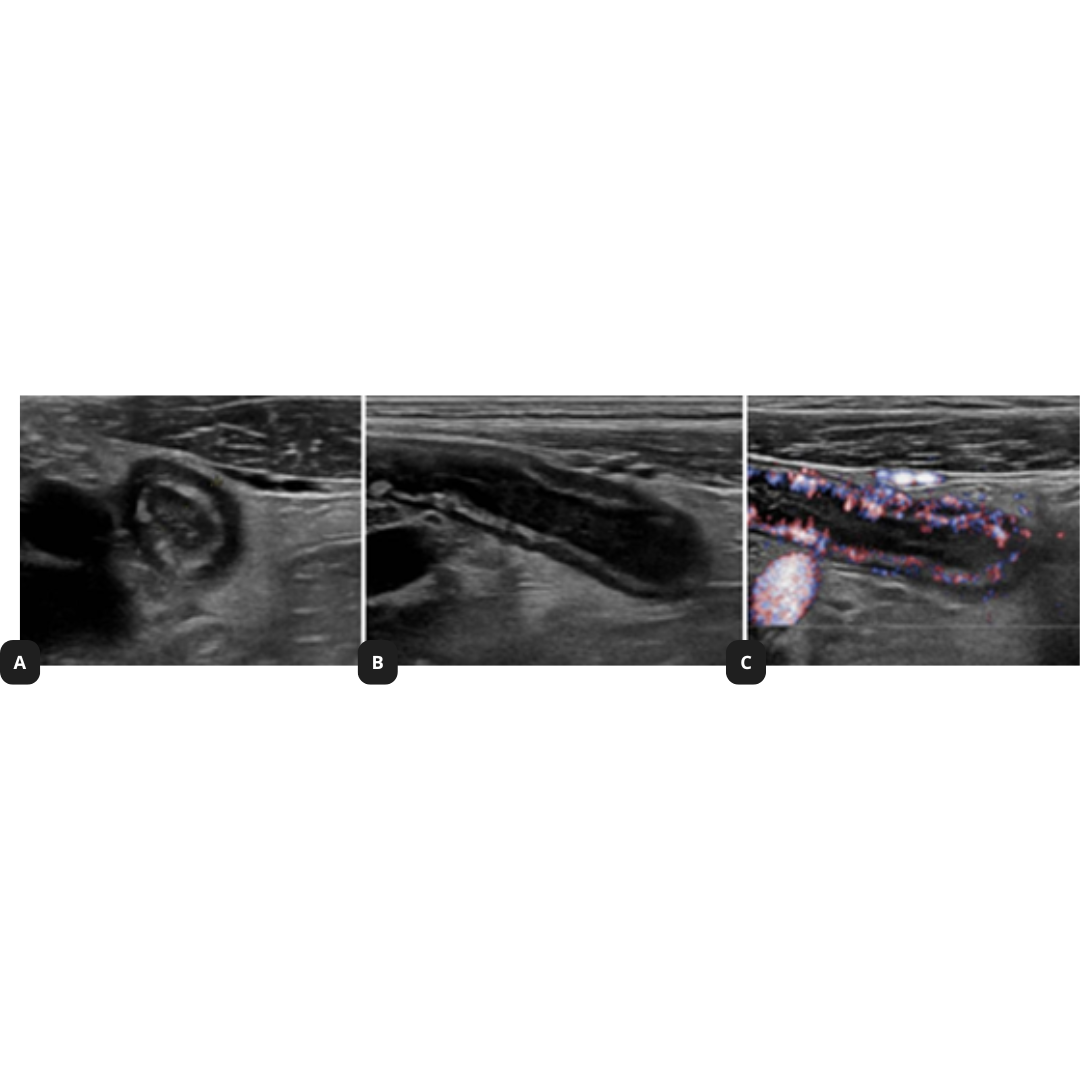

Signos US: aumento del diámetro del apéndice cecal (> 6 mm) y pared apendicular engrosada (> 3 mm), signo del fondo de saco ciego, apéndice no compresible, grasa peri apendicular hiperecogénica, la señal al Doppler color dependerá del estadio evolutivo (en fase aguda existirá hiperemia), puede existir apendicolito asociado.

Figura 1: Apéndice cecal aumentado de tamaño, con hiperemia y grasa periapendicular hiperecogénica. En B y C se observa el signo del fondo de saco ciego característico de afectación apendicular.